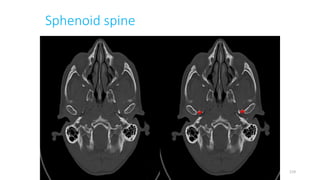

SPHENOID SPINE, LEFT

105

Sphenoid spine

119

Sphenoid spine (right)

133